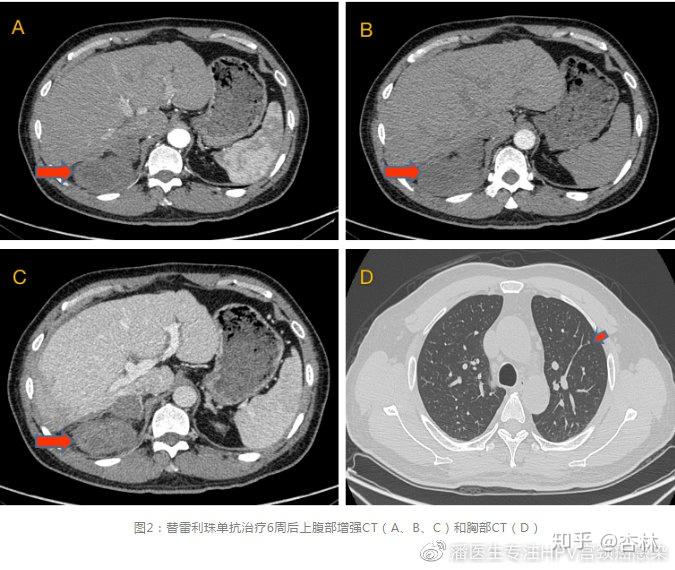

病例分享无进展生存期达14个月免疫治疗复发转移肝细胞癌一例